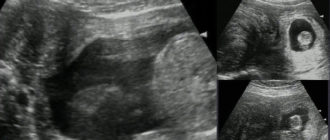

Размер миомы матки в неделях Миома матки представляет собой опухоль доброкачественного характера, появляющаяся в

Как протекает беременность при миоме? Миома матки представляет собой одну из самых распространенных разновидностей